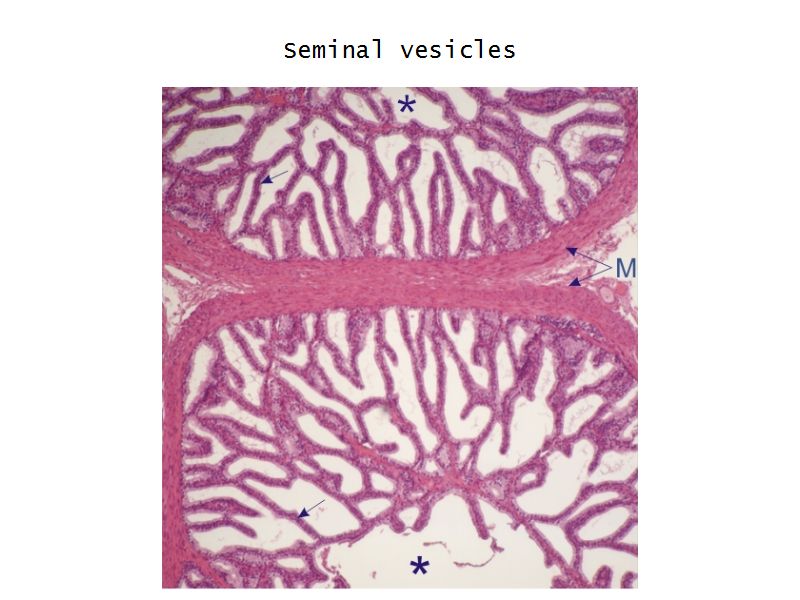

Vesicula seminalis

Slide 81Vesicula seminalis

- Mucosa

- Epithelium

- Lamina propria

- Muscle layer

Mucosa

- Lumen

- Irregular

- Store secretions

- Pseudostratified columnar epithelium

- Lamina propria

- Contains AVL

- Folded mucosa ^^ surface area

Muscle layer

- Inner circular

- Outer longitudinal